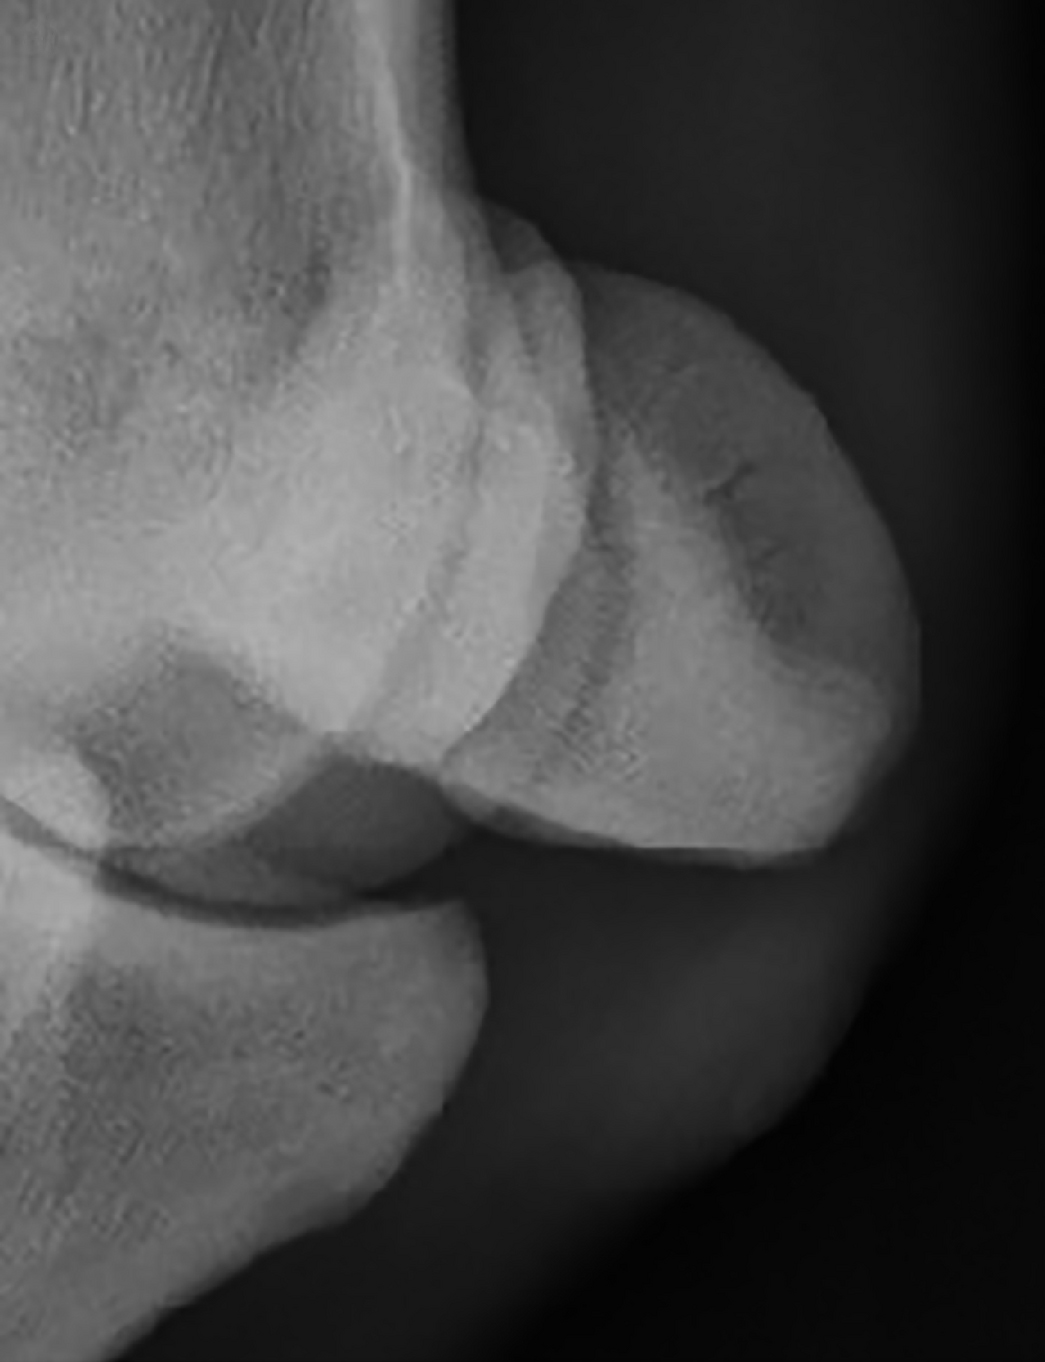

Association between sesamoiditis, subclinical ultrasonographic suspensory ligament branch change and subsequent clinical injury in yearling Thoroughbreds

This prospective study aimed to investigate the associations between radiographic signs of sesamoiditis, ultrasonographic signs of suspensory ligament branch desmitis and subsequent clinical suspensory ligament branch injury (SLBI).

Before commencing training, 50 yearling Thoroughbreds from a single training facility were evaluated. Radiographic changes in sesamoid bones were graded on a scale of 0 to 5: Changes of Grades 2-5 were considered as possibly significant sesamoiditis. Ultrasonographic changes in the forelimb suspensory ligament branches were graded from 0 to 3, with Grades 2-3 considered as possibly significant. Further imaging was performed only if clinical SLBI occurred over the course of the subsequent 9 months.

The prevalence of Grade 2-5 sesamoiditis in initial radiographs was 20.5% (Observer 1) and 23% (Observer 2) of all 200 sesamoid bones assessed. The prevalence of Grade 2-3 suspensory ligament branch change was 18.5% (Observer 1) and 23% (Observer 2). Once adjustments were made for interobserver differences, there was a significant association between Grade 2-5 sesamoiditis and Grade 2-3 suspensory ligament branch injury.

28% of sesamoids with Grade 2-5 sesamoiditis also had Grade 2-3 suspensory ligament branch change of Grade 2-3, compared with 4% of sesamoids considered to be normal. Eight horses developed clinical SLBI, of which 5 had Grade 2-5 sesamoiditis and Grade 2-3 suspensory ligament branch change at initial imaging assessment. When considered separately from each other, both Grade 2-5 sesamoiditis and Grade 2-3 suspensory ligament branch change were significant risk factors for subsequent SLBI. When these occurred concurrently, there was a significantly increased risk of clinical SLBI.